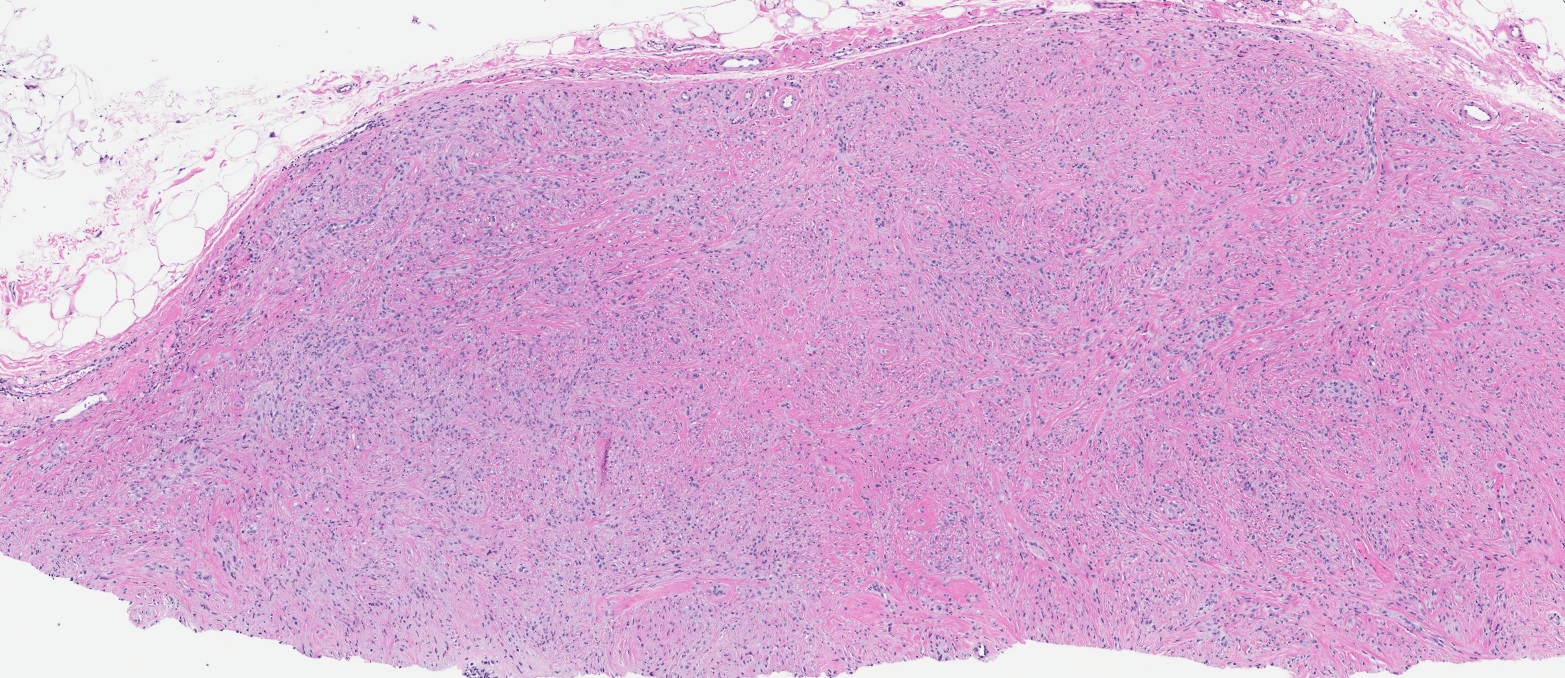

Microscopic (histologic) images

- Well circumscribed, lacks true capsule, rarely infiltrative

- Bland, uniform, short to elongated spindle cells arranged as short haphazard intersecting fascicles admixed with bands of hyalinized, brightly eosinophilic collagen and variable amounts of fat